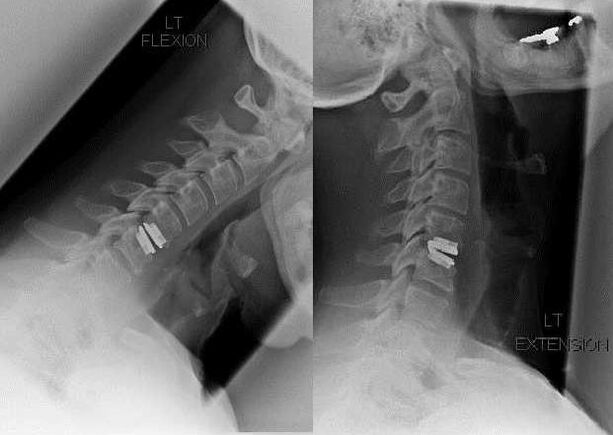

Operation

Zu den Indikationen für einen chirurgischen Eingriff zählen die Unwirksamkeit einer konservativen Behandlung sowie Komplikationen der zervikalen Osteochondrose, beispielsweise diskogene Myelopathie, Wirbelarteriensyndrom und radikuläres Syndrom. Um das Rückenmark, die Blutgefäße und die Wirbelsäulenwurzeln zu entlasten, werden folgende Operationen durchgeführt:

Bei der Operation können Knochenfragmente und Bänder entfernt sowie Bandscheiben ganz oder teilweise entfernt werden. Bei kleinen Hernienvorsprüngen wird häufig eine Laserverdampfung des Bandscheibenkerns durchgeführt.

Nach der Entfernung von Wirbelstrukturen ist häufig eine Stabilisierung der Bewegungssegmente der Wirbelsäule durch eine Wirbelsäulenfusion oder die Installation von Knochen- und Hautautotransplantaten erforderlich.